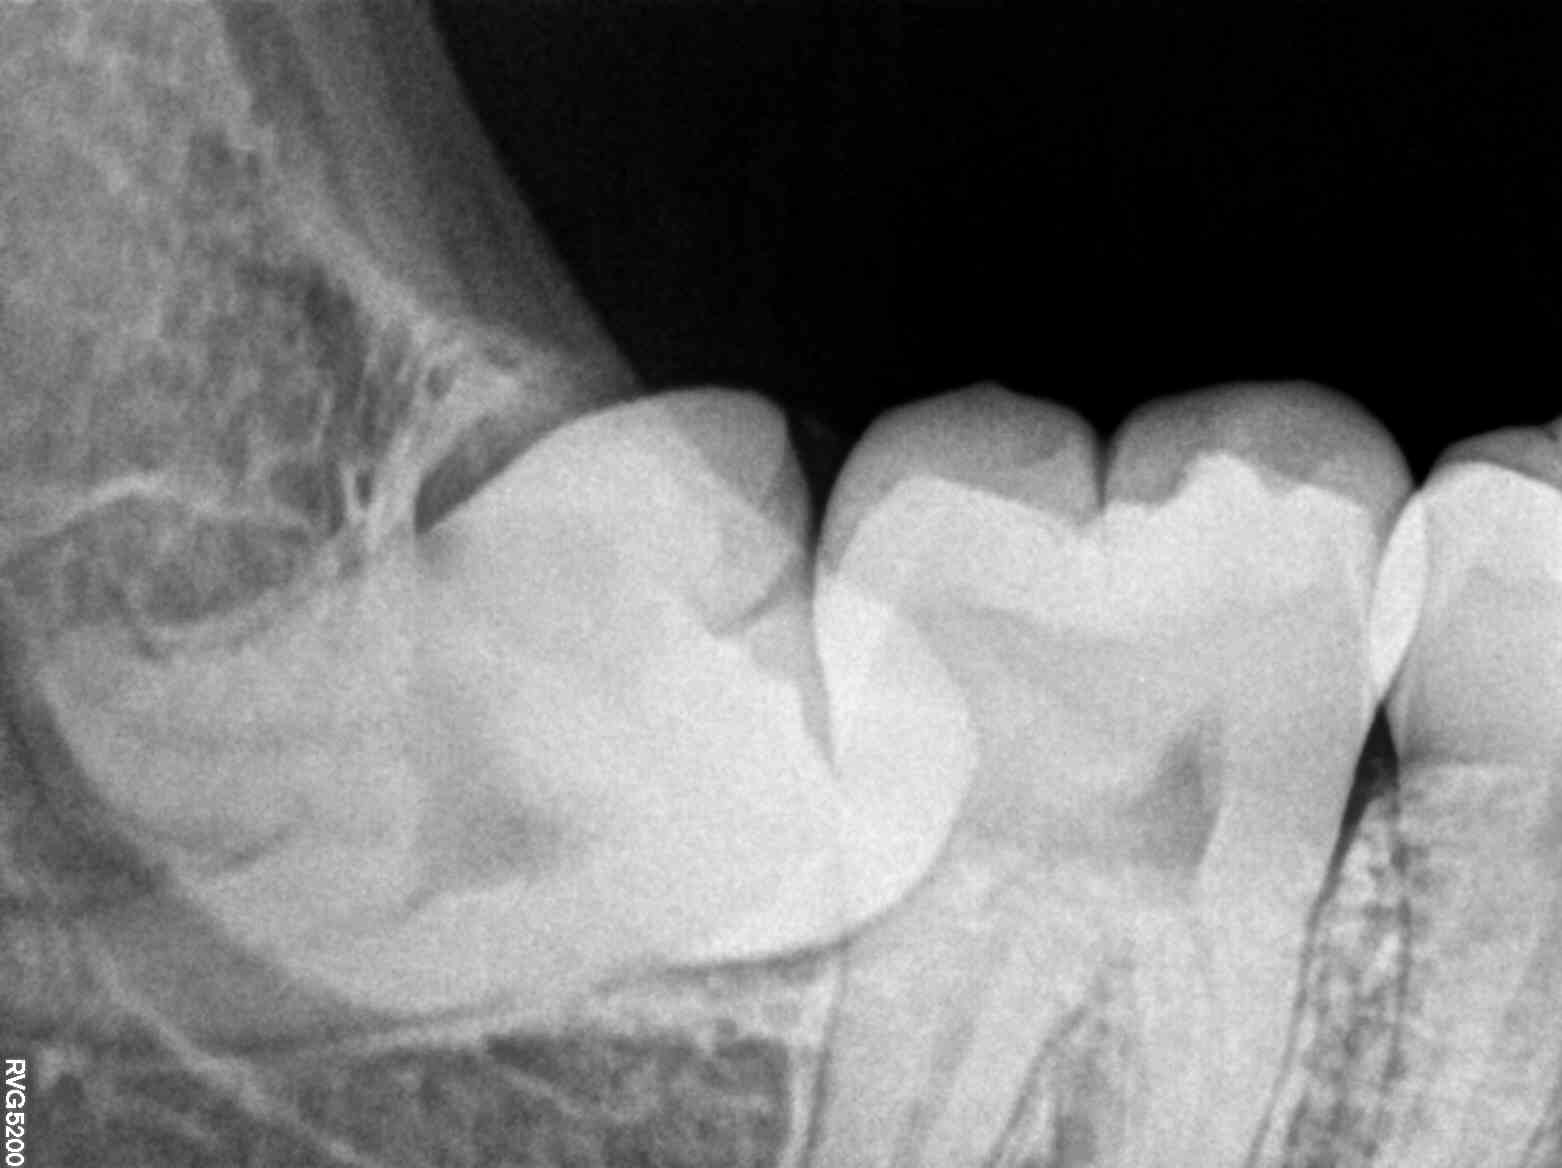

When Ananya first visited the clinic, she was greeted with genuine care and professionalism. The clinic's team understood her frustrations and patiently explained the process and benefits of their advanced X-ray services. The X-ray images revealed an underlying issue that had been overlooked—a misaligned wisdom tooth exerting pressure on her molars. This revelation was the key to developing a tailored treatment plan that would finally alleviate her pain.

For those dealing with persistent dental challenges, the solution may lie hidden beneath the surface. The advanced X-ray services offered by the clinic do more than just detect cavities; they provide a roadmap to oral health, guiding patients and clinicians towards effective treatment strategies.